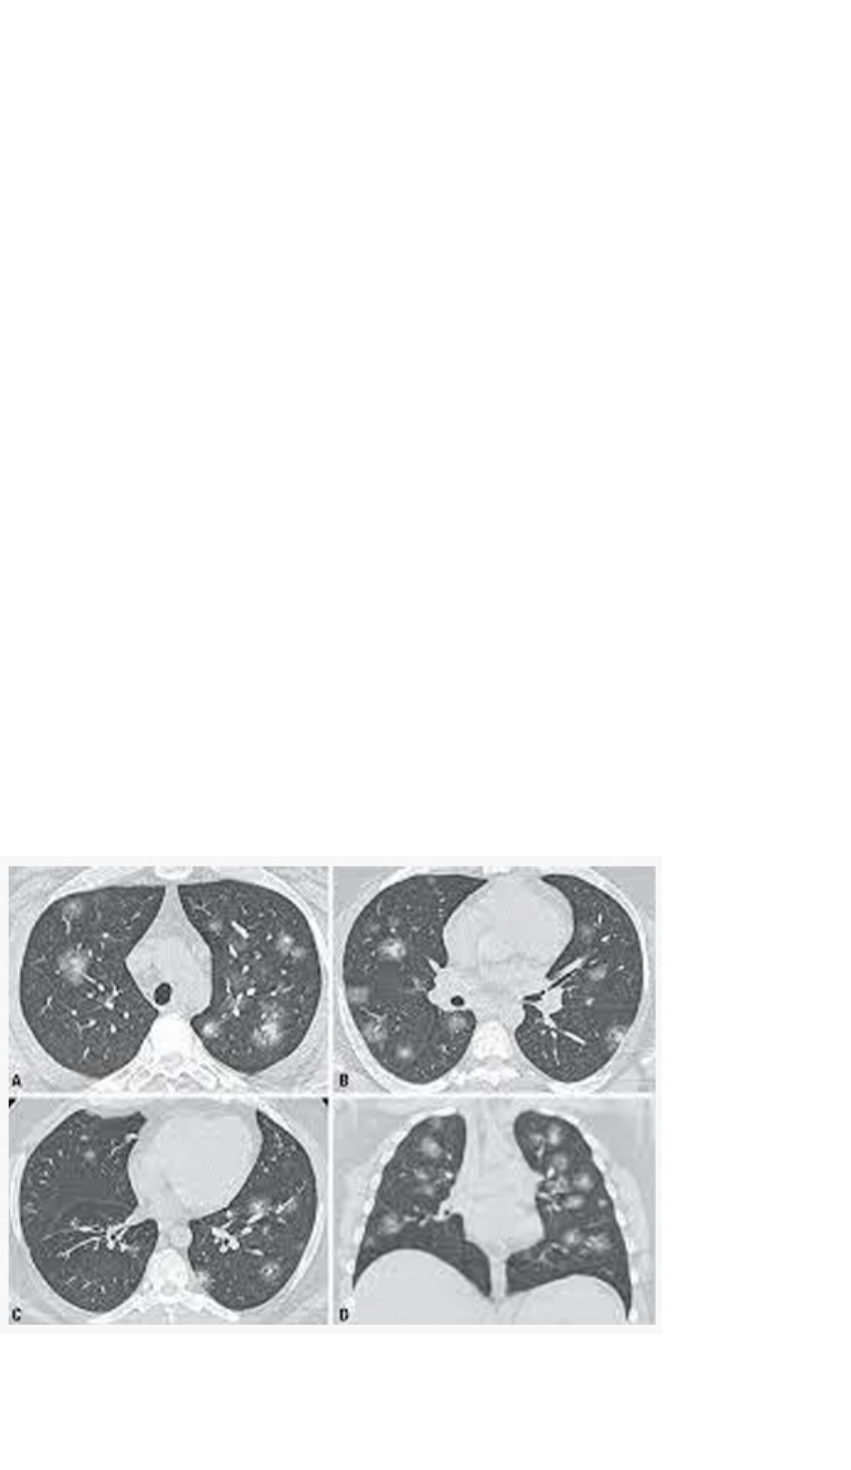

<p>ESTUDO DE CASO</p><p>Homem de 57 anos de idade chega ao hospital com febre, tosse seca e dificuldade para respirar. Ele também relata sentir muito cansaço musculoesquelético e mal estar. Ele tem história de hipertensão, que é controlada com enalapril, além de histórico de infarto no ventrículo esquerdo. Ao exame físico, seu pulso é de 120 bpm, sua temperatura é de 38.7 °C (101.6 °F) e sua saturação de oxigênio é de 88%. Ele parece agudamente doente. Ele é internado em uma sala de isolamento e passa a receber oxigênio, fluidoterapia intravenosa e profilaxia para tromboembolismo venoso. São solicitadas culturas de sangue e escarro. A radiografia torácica demonstra infiltrados pulmonares bilaterais e a tomografia computadorizada torácica revela múltiplas áreas lobulares e subsegmentares bilaterais com opacidade em vidro fosco (figura 1). Um swab nasofaríngeo é enviado para testes de reação em cadeia da polimerase via transcriptase reversa em tempo real, e o resultado é positivo para o coronavírus da síndrome respiratória aguda grave 2 (SARS-CoV-2) algumas horas mais tarde. Diante deste caso, responda:</p><p>Figura 1 - Tomografia Computadorizada infiltrados pulmonares bilaterais</p><p>Tomografia computadorizada com opacidade em vidro fosco no dia 1 após o início dos sintomas (figura superior A e B), e opacidade em vidro fosco bilateral e condensação no dia 7 após o início dos sintomas (Figuras C e D).</p><p>ATIVIDADE PROPOSTA</p><p>1) Quais são as funções do sistema comprometido neste caso.</p><p>O sistema respiratório está comprometido neste caso, e o mesmo tem como principal função a troca gasosa nos pulmões, o transporte de ar aos pulmões liberando o gás carbônico, por meio do ajuste da velocidade/profundidade da respiração regula o ph sanguíneo, e proteção contra agentes patogênicos.</p><p>2) Esquematize o trajeto do ar desde as narinas até os alvéolos.</p><p>· Narinas</p><p>· Cavidade nasal, onde o ar é umedecido, aquecido e filtrado.</p><p>· Faringe</p><p>· Laringe</p><p>· Traqueia</p><p>· Brônquios principais (direito e esquerdo)</p><p>· Brônquios lobares (três no pulmão direito, dois no esquerdo)</p><p>· Brônquios segmentares</p><p>· Brônquiolos</p><p>· Brônquiolos terminais</p><p>· Brônquiolos respiratórios</p><p>· Ductos alveolares</p><p>· Sacos alveolares</p><p>· Alvéolos, onde ocorre a troca gasosa.</p><p>3) Com base no caso, diferencie anatomicamente os pulmões quando aos lobos e fissuras.</p><p>Pulmão Direito: Tem três lobos (superior, médio e inferior) separados por duas fissuras (a fissura obliqua e a fissura horizontal).</p><p>Pulmão Esquerdo: Tem dois lobos (superior e inferior) separados por uma única fissura (a fissura obliqua). O pulmão esquerdo também possui uma estrutura chamada língula, que é uma extensão do lobo superior.</p><p>4) Qual plano de corte é visualizado na figura 1c e 1d?</p><p>Cortes tomográficos axiais, que são transversais ao corpo, o que confirma que a estrutura foi cortada de baixo para cima e proporciona uma visão detalhada de cima para baixo dos pulmões.</p><p>5) Diante do cansaço musculoesquelético e do histórico de hipertensão arterial, diferencie os esses dois tipos de músculos. Com relação ao órgão envolvido com a hipertensão, mencione os nomes das camadas que o compõem.</p><p>· Músculo Esquelético: É voluntário, estriado e responsável pelos movimentos do corpo e postura, estando ligado aos ossos.</p><p>· Músculo Cardíaco (miocárdio): É involuntário, estriado e realiza contrações fortes, contínuas e rítmicas que são geradas automaticamente e serve para bombear sangue.</p><p>O órgão envolvido com a hipertensão é o coração, cujas camadas são:</p><p>· Endocárdio: revestimento interno.</p><p>· Miocárdio: camada muscular média, responsável pela contração.</p><p>· Epicárdio: camada externa que também faz parte do pericárdio visceral.</p><p>6) Tendo em vista o histórico de infarto apresentado pelo paciente, esquematize a circulação envolvida com a câmara cardíaca citada no texto</p><p>A circulação coronariana supre o miocárdio (músculo cardíaco), incluindo o ventrículo esquerdo. A artéria coronária direita e esquerda, ramificam-se da aorta logo acima da válvula aórtica. Os ramos da artéria coronária esquerda incluem a artéria interventricular anterior e a artéria circunflexa, que suprem o ventrículo esquerdo. As veias cardíacas drenam o sangue usado pelo músculo cardíaco de volta ao coração, terminando no seio coronário, que deságua no átrio direito.</p><p>CONCLUSÃO</p><p>Ao final do seu trabalho, você deverá realizar individualmente uma conclusão, expressando seu ponto de vista sobre os desafios durante o desenvolvimento do trabalho.</p><p>Foi desafiador estudar sem o suporte diretor do professor, aquele “bate-bola” em sala de aula, mas ainda assim consigo filtrar muito bem as informações passadas pelo Prof. Fábio – a didática dele é sensacional. Estou me readaptando e buscando me atualizar com novas fontes de pesquisas, as o conteúdo do livre dar um norte para saber o que procurar.</p><p>image1.png</p>